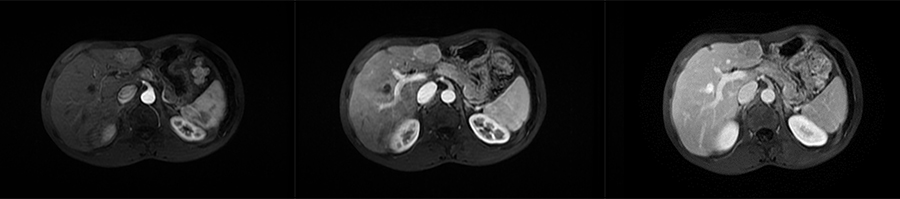

▲ 患者一计划进针路线

▲ 患者二计划进针路线